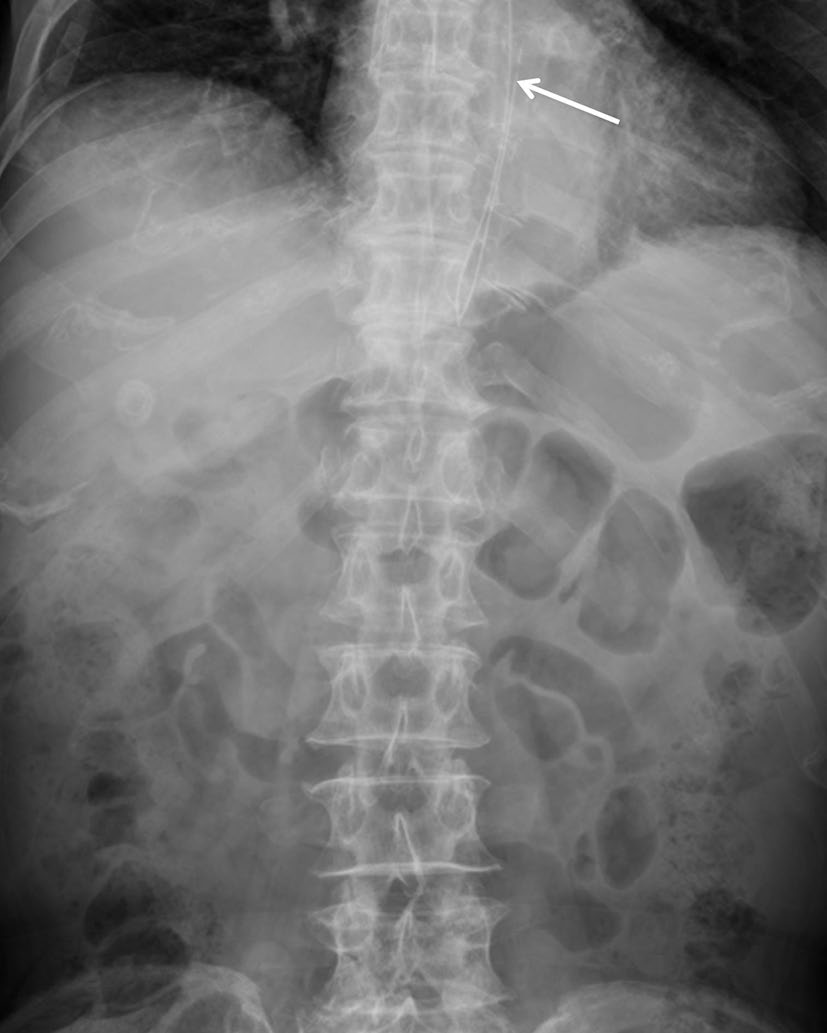

骨折

某些医疗器械的断裂可能与器械材料、植入时间、器械所处的解剖结构以及任何相关操作有关。支架断裂的报道发生率偏低,可能是由于意识不足以及对事件检测困难所致。胆道或胃肠道支架的断裂可能自发发生,也可能由用于治疗肿瘤再生的球囊扩张或氩等离子凝固引起(图16)[10]。这些断裂可能导致胃肠道出血、复发性胆道梗阻、肠梗阻或穿孔。